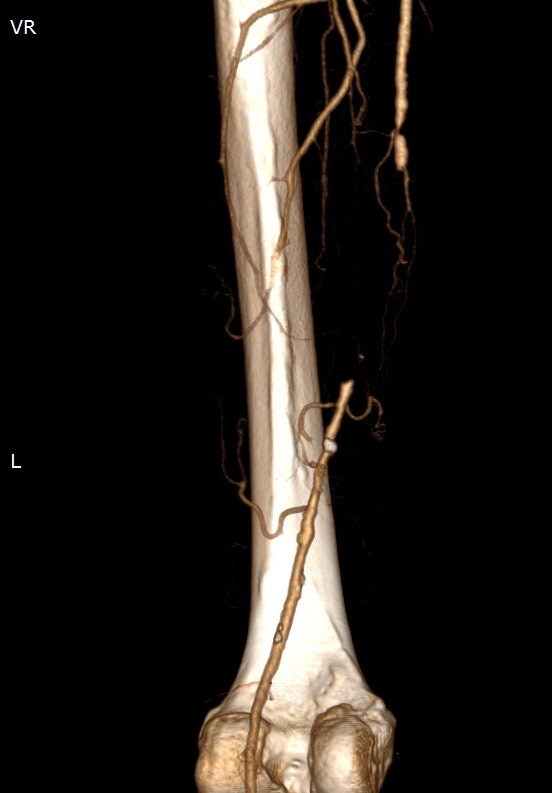

2186. Для лечения пациента с хронической окклюзией пба слева (снимок мскт), клиникой перемежающей хромоты, хинк iib рекомендуется